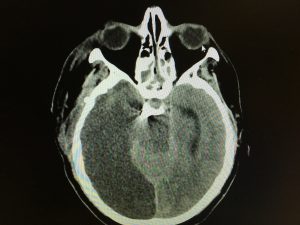

Patologia cerebrovascolare acuta

- emorragie intraparenchimali spontanee (ICH);